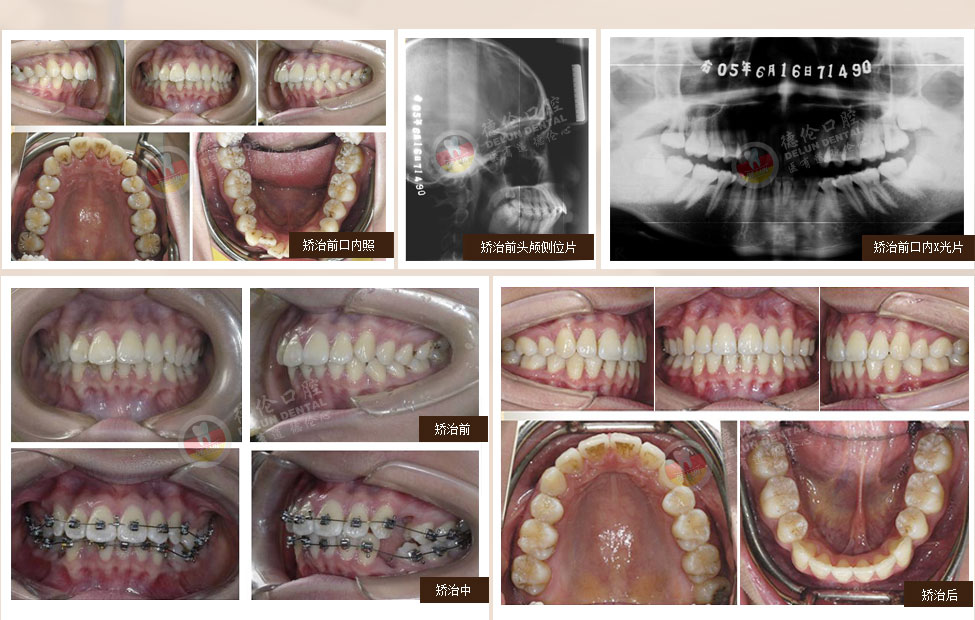

• 女:13歲

癥狀:上下前牙前突、唇傾,上下牙弓散在間隙

矯治方法:SPEED矯治器結合種植釘、整體內收上下牙弓、改善雙牙弓前突以及凸面型側貌